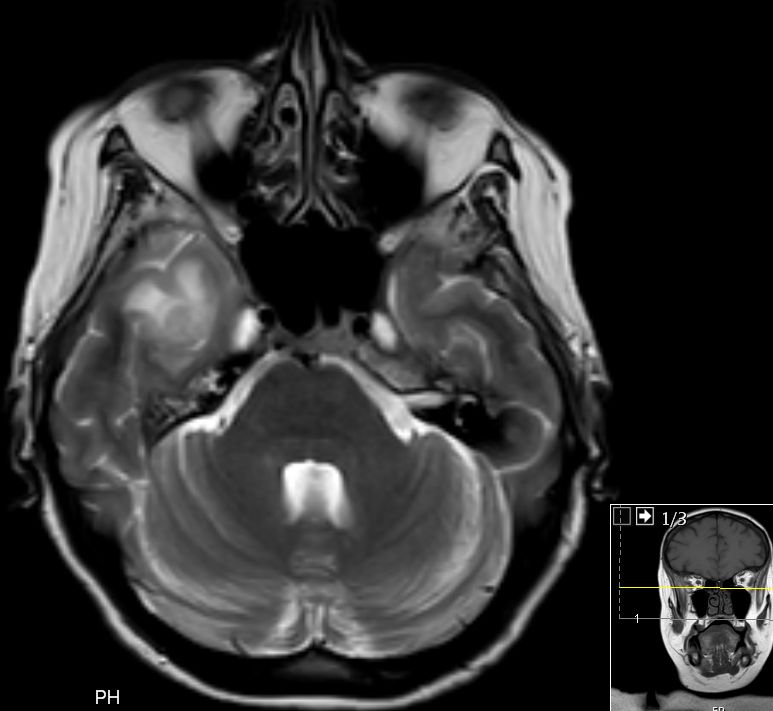

| paraaortale Lymphknoten - Metastasen | 54-jährige Frau, die vor 4 Jahren wegen eines

Zervix - Karzinoms FIGO IIIb mit Radiochemotherapie behandelt wurde. Damals praevesikaler Harnstau beiderseits. Jetzt neu Harnstau links. RF links paraaortal. ![]() | |||

![]() |

![]() | |||